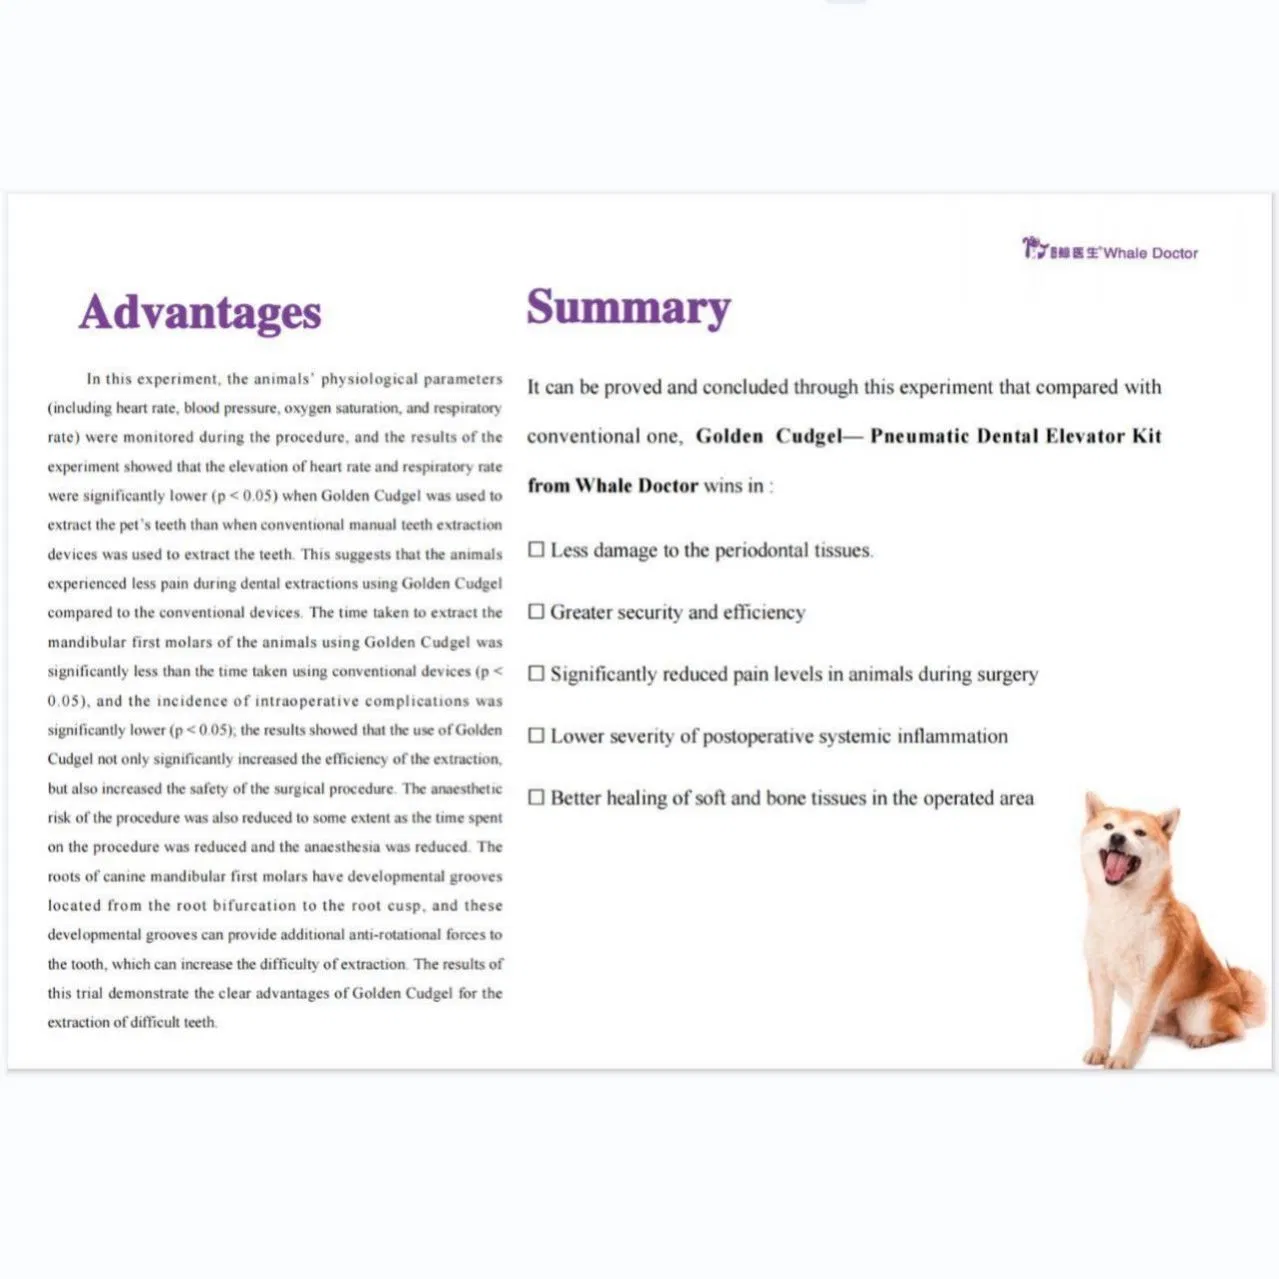

This study evaluated the effectiveness of state-of-the-art dental tools for veterinary use. The treatment group utilized the revolutionary Pneumatic Dental Elevator Kit. Critical factors observed included physiological parameters, intraoperative complications, extraction duration, and socket damage. Rigorous statistical analysis highlights the superior performance of these advanced tools.